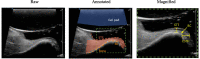

Background: Ultrasound is a non-invasive, cross-sectional imaging technique emerging in dentistry. It is an adjunct tool for diagnosing pathologies in the oral cavity that overcomes some limitations of current methodologies, including direct clinical examination, 2D radiographs, and cone beam computerized tomography. Increasing demand for soft tissue imaging has led to continuous improvements on transducer miniaturization and spatial resolution. The aims of this study are (1) to create a comprehensive overview of the current literature of ultrasonic imaging relating to dentistry, and (2) to provide a view onto investigations with immediate, intermediate, and long-term impact in periodontology and implantology.

Results: A critical review of the clinical applications of ultrasound in dentistry was provided with a focus on applications in periodontology and implantology. The role of ultrasound as a developing dental diagnostic tool was reviewed. Specific uses such as soft and hard tissue imaging, longitudinal monitoring, as well as anatomic and physiological evaluation were discussed.